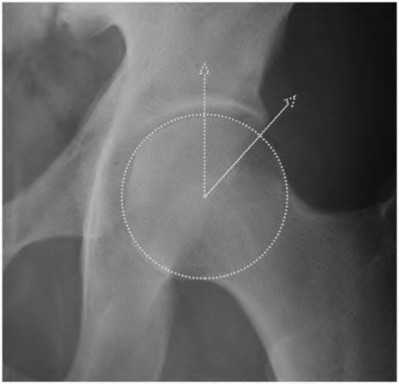

A 72-year-old female presents with progressive left thigh and knee pain for the last year. 5 years ago she sustained a femoral neck fracture treated with the implant seen in Figures A-C (current radiographs). The thigh pain is worse with weight-bearing. C-reactive

protein and erythrocyte sedimentation levels are within defined limits. Which of the following is the most likely cause of her pain?